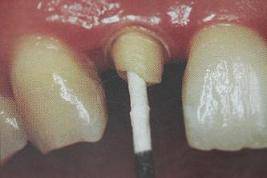

为了提高固位力,纤维桩选择考虑到三个因素:一是透明度,二是表面处理(粗化和硅烷预处理),三是固位形态的设计。特别是纤维桩根端部分的螺纹型结构可显著提高桩在根管内的机械固位,防止纤维桩脱落。

纤维桩试放时应用镊子夹持将其插入预备的根管桩道中(这涉及无菌观念和操作),就位时无阻力可稍有锢住感。